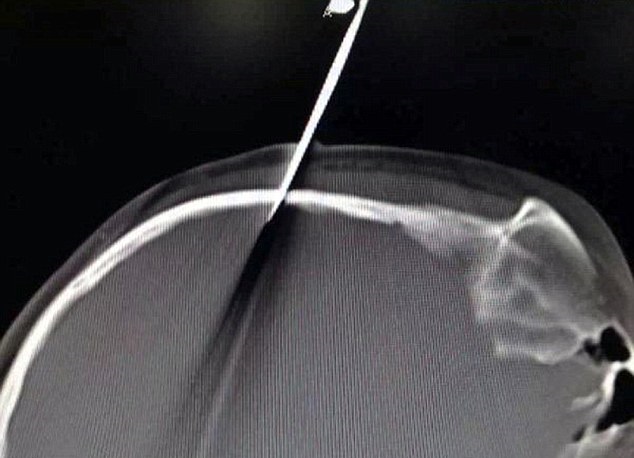

به گزارش دیلیمیل، دختر 10 ساله سریعا به بیمارستان انتقال داده شد در حالی که قیچی 6 اینچ در سرش فرو رفته و در همان حالت ثابت مانده بود. علت این کار هم بازیگوشی دخترک هنگام درس خواندن بوده که البته دخترک چیزی به یاد نمیآورد.

پزشکان اعلام کردند که دخترک بسیار خوششانس بوده چرا که نوک قیچی با فاصله بسیار کمی از رگ اصلی عبور کرده و آن را سوراخ نکرده است.